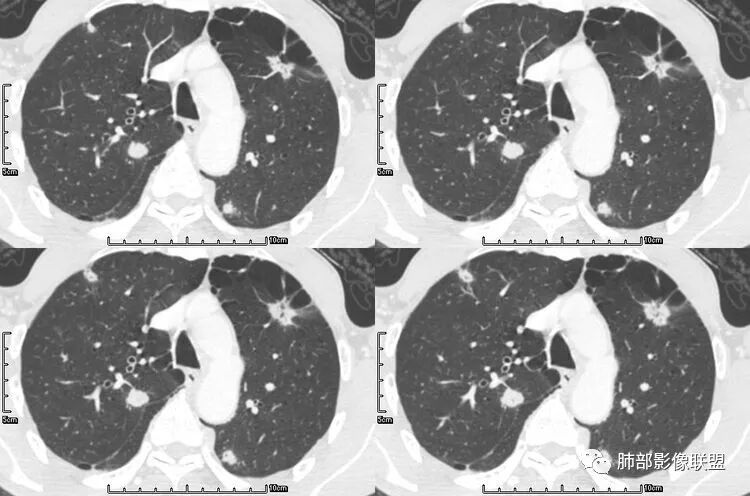

张延军:双肺多发结节,空洞影,后者洞壁厚薄不均匀,部分腔内丝丝落落,呈分叶征,边缘见毛刺影,病灶大部分位于胸膜下,与血管相连,右肺下叶前基底段结节近段支气管截断,远端见空腔。左肺下叶病灶密度不均,背段支气管壁增厚,管腔狭窄。考虑1.双肺下叶占位性病变伴肺内空洞性转移 2.多原发的占位 3.肉芽肿性血管炎代排。

背景是慢阻肺背景。病灶是多发结节伴空洞,内部见结节影,即空洞内结节,符合得有:GPA,癌,结核,真菌(隐球菌,曲霉)

脐凹征、粗短毛刺、深分叶、中央结构杂乱

本病例左肺下叶肿块,有深分叶、毛刺、胸膜牵拉凹陷、支气管截断及纵隔内淋巴结肿大等征象,都均支持病灶为恶性,如腺癌,而且叶间裂的多发结节也提示是腺癌来源可能大;双肺多发结节、肿块,大部分病灶有分叶、毛刺及胸膜凹陷的恶性征象,与原发肿瘤本身的性质有关,所以应该与左肺下叶肿块同源,而且双肺多发病灶内空洞也具有多样性;